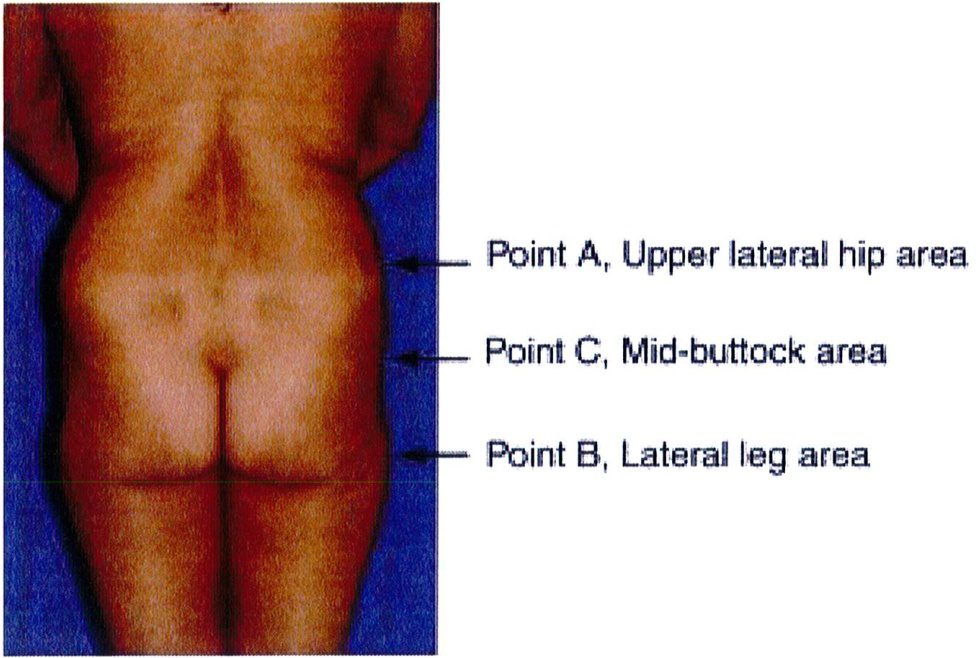

Việc phân loại các loại khung được thực hiện bằng cách so sánh và đối chiếu lượng chất béo có sẵn trong 3 vùng cụ thể. Điểm nhô ra nhất ở vùng hông, giới hạn trên được đánh dấu là điểm A, điểm nhô ra nhiều nhất ở vùng đùi ngoài

là điểm B và điểm giữa mặt ngoài mông là điểm C (Hình 4).